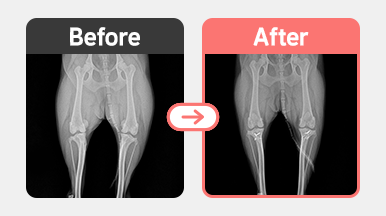

[슬개골 탈구 수술] 포메라니안 / 4살 / 양측 슬개골탈구 2기

2025-11-28